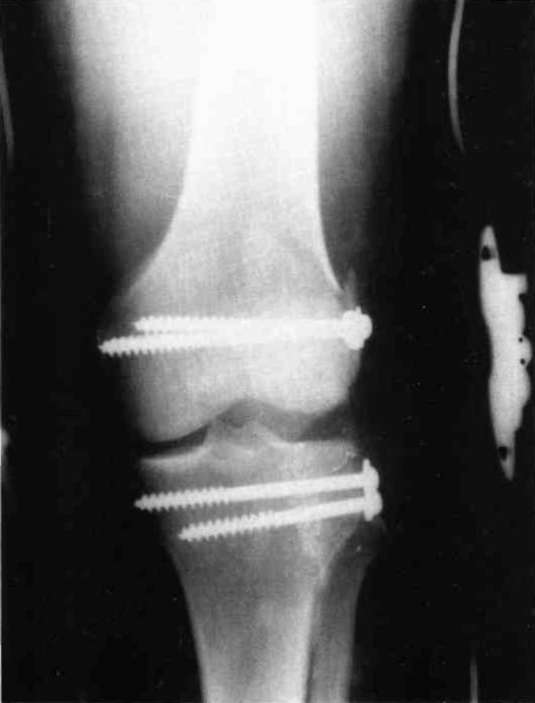

A nineteen year old male sustained a distal fracture with a split condylar fracture to the right leg (Fig. 10) and a lateral condyle fracture on the contralateral side (Fig. 11). Fractures were stabilized, but were not internally fixed at time of admission because of emergency vascular repairs being required. Three days post injury, the patient underwent ORIF of his fractures (Fig. 12 and Fig. 13). The right leg was placed in a free knee Mobilizing Brace and the left leg was placed in the rehabilitative free knee orthosis. A continuous passive motion dynamic suspension system was placed on the lower right extremity (Fig. 14). The lower left extremity had normal pain free motion following surgery. The patient was kept in passive motion for five days and achieved 0-100° of pain free motion. A cast brace was applied on the right extremity; the patient received gait training and was discharged.

Figure 12:

Figure 13: